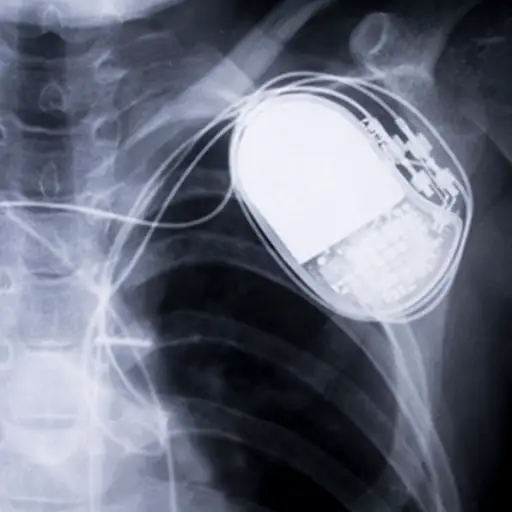

当心肌需要重复,甚至是连续,提醒搏动的顺序,而药物是不够的,不同设备可以帮助。心脏起搏器和植入式心脏复律除颤器(ICDs)这两种设备使医疗专业人员能够根据需要控制病人的心率和泵送能力——准确地在心律失常发生的时候。

设备续。

起搏器可能是临时的或永久性的,内部或外部电池发生器和皮肤下的引线(电线)。这些引线发送电信信息定期收缩心肌。反过来,去纤颤器提供低电击可以重置不规则心跳,大电击可以对抗危险的室性心律失常。与心脏起搏器一样,心脏除颤器使用电池并插入心脏,但该设备被放置在胸部或腹部的皮肤下。